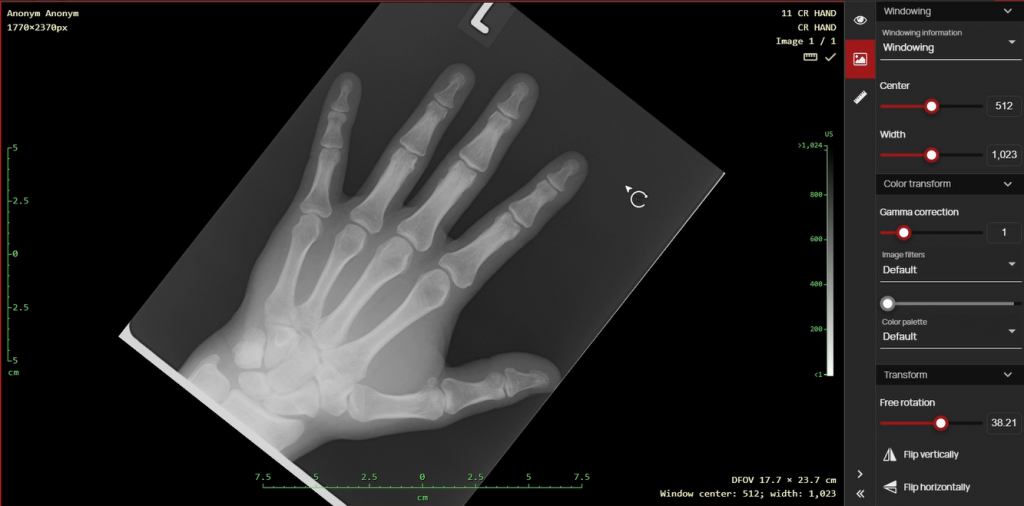

- Electronic pencil this digitizing tool is used to draw objects into the edited image or video, namely a free drawing, ellipse or arrow with a note.